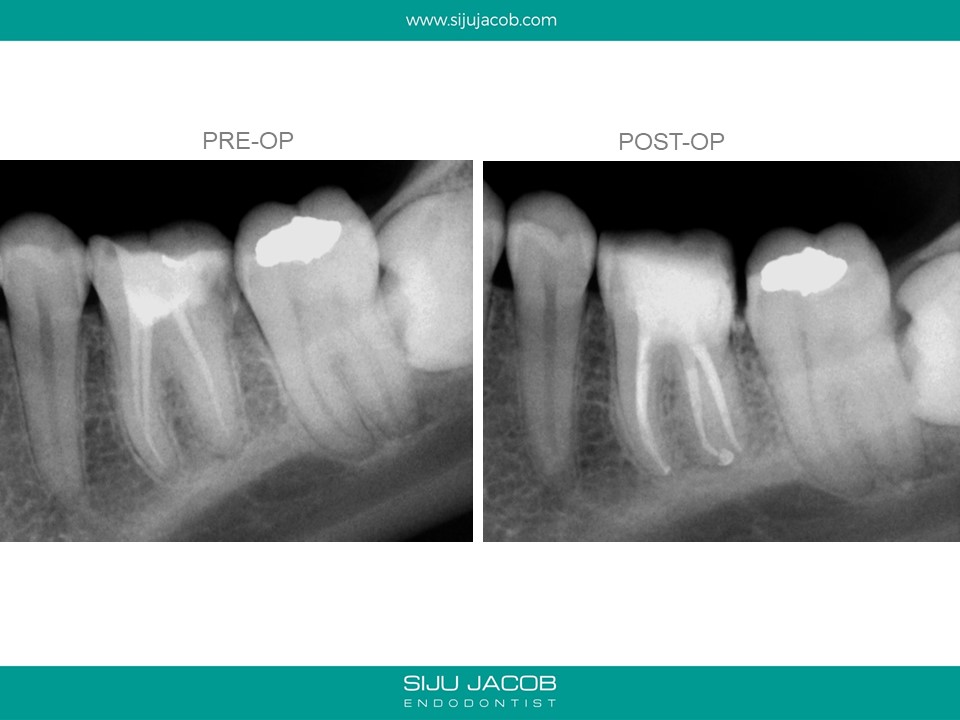

This patient had sensitivity to cold after an RCT on a lower molar. Sensitivity persisted even after a month. Re-treatment revealed a missed distal canal/root that was still vital and hyperaemic.